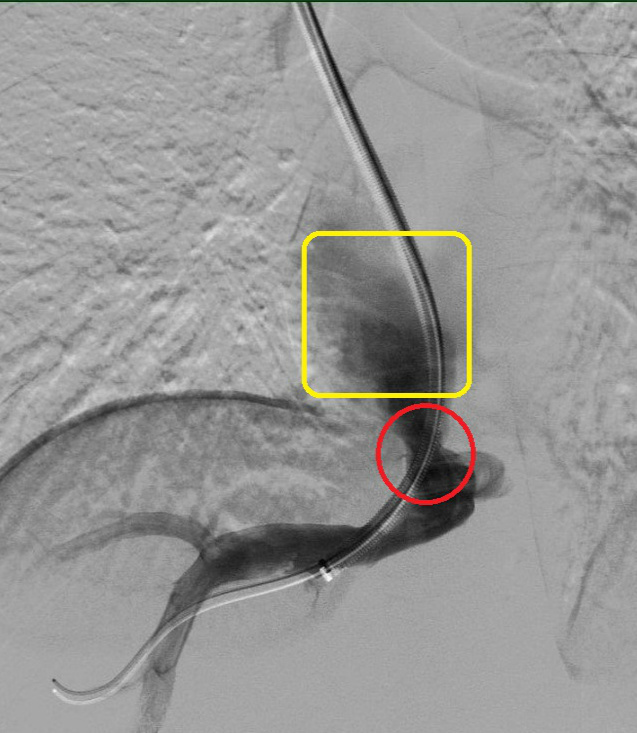

术后

红色圈内为打通后的静脉,可见血管较前明显增宽,远端黄色方框内可见大量血流通过。